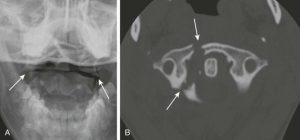

Диагностика: рентгенограмма осуществляется через рот (выполняется через открытый рот пациента, именно в этом положении можно увидеть первый, второй позвонки и их взаимоотношение); КТ.